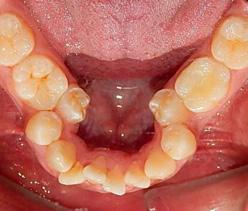

Estudios de inicio intraorales en la fotografía de frente, tenemos la línea media dental superior se encuentra desviada a 1 mm a la izquierda y la línea media dental inferior se encuentra desviada 2 mm a la derecha (Figura 2). En la oclusal superior la forma de arco cuadrada (Figura 3). En la lateral derecha una relación molar clase II y relación canina clase II (Figura 4), izquierda una relación

molar clase II y relación canina clase II.

Figura 3. Oclusal superior. Figura 4. Derecha, izquierda. Figura 5. Izquierda inicio. Figura 6. Radiografía lateral de cráneo y radiografía panorámica.